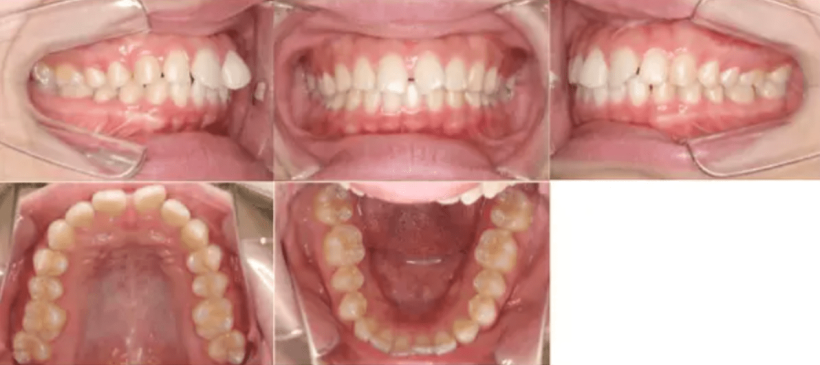

治療内容 前歯に隙間があり、ねじれてしまっていたため、マウスピース矯正で治した。

治療期間 6カ月

費用 40万円

【治療後】

治療例①②のように部分矯正によって改善された事例もありますが、部分矯正から全顎矯正に変更したことで歯並びが揃った症例もあります。